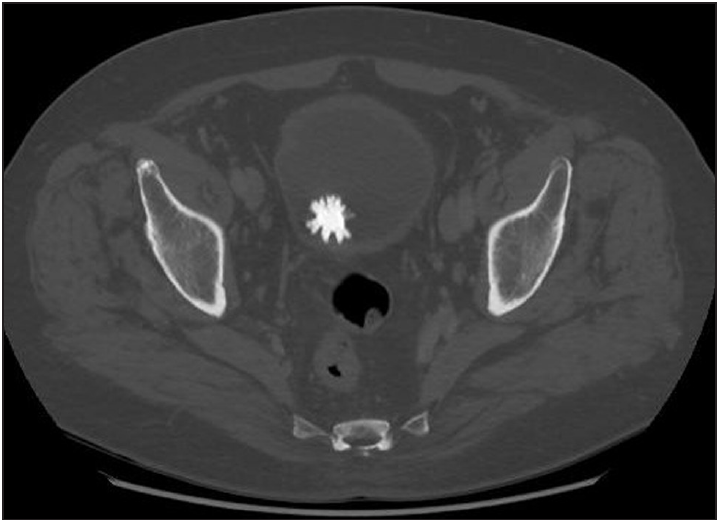

Imaging Tests: Ultrasound, CT Scans, and X-Rays

Diagnosis is done by X-ray, computer tomography (CT) scan, or ultrasound. These imaging tests create a picture of the bladder and urinary tract and detect the location and size of bladder stones10.